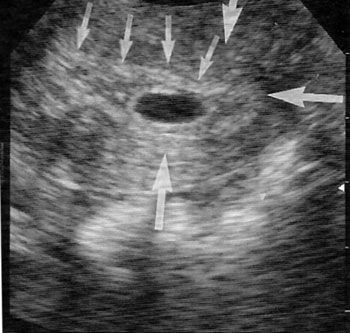

Εικόνα 3α. Αληθής εμβρυϊκός

σάκος. Ενδομήτριο (μικρά βέλη). Διπλή ηχητική απεικόνιση του περιγράμματος του

σάκου, που οφείλεται στον ηχητικό διαχωρισμό του αληθούς φθαρτού από το ανεστραμμένο

(μεγάλα βέλη). Ο σάκος εμφανίζεται σαν κάτι ξεχωριστό στο ενδομήτριο. β. Ψευδοσάκος.

Ενδομήτριο (μικρά βέλη), φθαρτοειδής αντίδραση (μεγάλα βέλη). Ο σάκος αποτελεί

συνέχεια του ενδομητρίου.

ΨΕΥΔΗ

ΑΡΝΗΤΙΚΑ ΥΠΕΡΗΧΟΓΡΑΦΙΚΑ ΣΗΜΕΙΑ

Σάκοι ψευδοκύησης

Ο σάκος ψευδοκύησης ορίζεται ως ένας σάκος με ενδομήτριο υγρό, που δεν περιβάλλεται

από διπλό φθαρτοειδή δακτύλιο ή δεν περιέχει λεκιθικό σάκο, ενώ ανευρίσκε σε

8% έως 29% των περιπτώσεων με εξωμήτρια κύηση (εικόνα 3). Η επισήμανση του σημείου

διπλού φθαρτοειδούς σάκου ή εμβρυϊκής ανάπτυξης, βοηθά συχνά στη διάκριση των

σάκων ψευδοκύησης από κανονικούς ενδομήτριους σάκους κύησης, αλλά μπορεί να

αποδειχθεί προβληματική στη διαφορική διάγνωση μεταξύ σάκων ψευδοκύησης και

παλίνδρομης κύησης, κατά τις πρώτες εβδομάδες.(22-23)